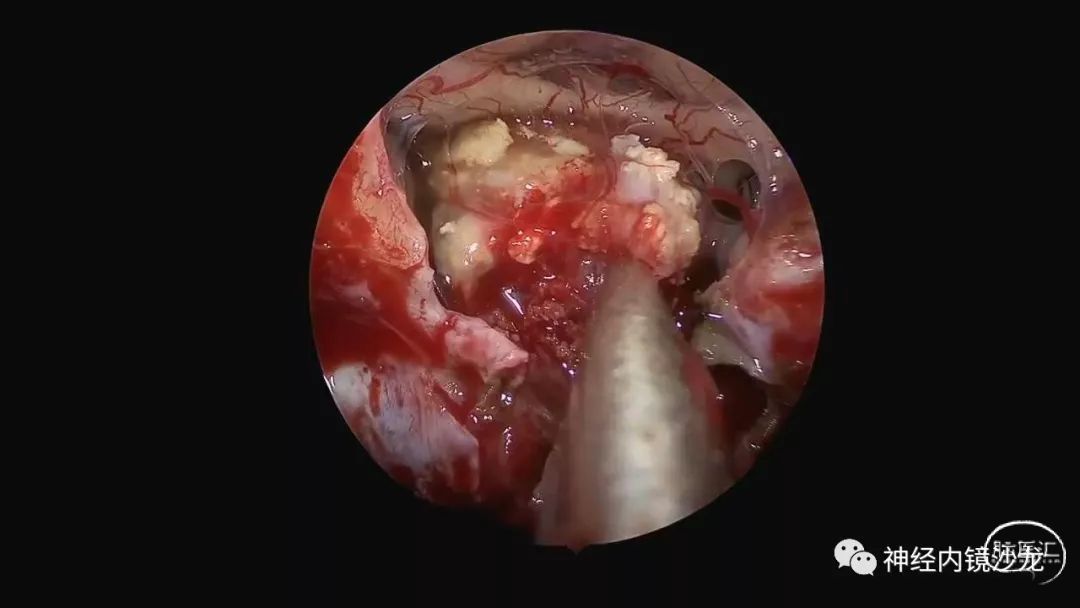

精彩图表

从事神经外科十余年,擅长神经外科肿瘤诊治,尤其是神经内镜微创手术治疗垂体瘤、颅咽管瘤、脑膜瘤等颅底肿瘤